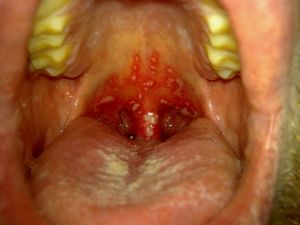

구내염은 구강 점막에 염증이 생기는 질환으로, 세균, 바이러스, 곰팡이 감염, 기계적, 온열적, 화학적 자극, 전신 질환, 영양 불균형, 호르몬 변화 등 다양한 원인에 의해 발생한다. 주요 증상으로는 구강 점막의 발적, 종창, 작열감, 구취, 물집, 궤양 등이 나타나며 심한 경우 통증, 발열, 저작, 연하, 발음 장애가 발생할 수 있다. 구내염은 재발성 아프타성 구내궤양, 헤르페스성 구내염, 편평태선, 칸디다증 등 다양한 유형으로 분류되며, 영양 결핍, 입꼬리염, 의치 관련 구내염, 알레르기성 접촉 구내염, 이주성 구내염, 헤르페스 치은구내염, 방사선 및 화학 요법, 괴사성 궤양성 치은구내염, 구강 니코틴염, 만성 궤양성 구내염, 형질 세포 치은구내염 등 다양한 형태로 나타날 수 있다. 치료는 국소 치료, 전신 치료, 생활 습관 개선을 통해 이루어진다.

구내염의 원인은 세균, 바이러스, 진균(眞菌) 등의 감염에 의한 것이 많고, 대체로 구강 위생이 불결한 경우에 나타난다. 또 의치 등에 의한 기계적 자극, 뜨거운 음식에 의한 온열적 자극, 약품에 의한 화학적 자극 외에 전신질환, 영양 불량, 임신과 사춘기, 폐경 등으로 인한 호르몬 변화,[26] 저항력이 떨어졌을 때에도 발생한다. 증세는 구강 점막의 발적(發赤), 종창, 작열감(灼熱感), 구취, 물집, 궤양 등이 생기고 통증이 심하다. 중증이면 발열하고 음식물을 씹거나 삼키는 것, 발음 장애를 일으키며, 유아는 영양 장애가 있기 쉽고 국소(局所) 림프절도 부어오른다.